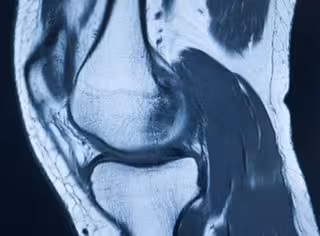

Imagen médica de articulación de rodilla.

Imagen médica de articulación de rodilla. - COPRIGHT PHOTOGRAPHER EDWARD OLIVE WEBSITE WWW.EDW